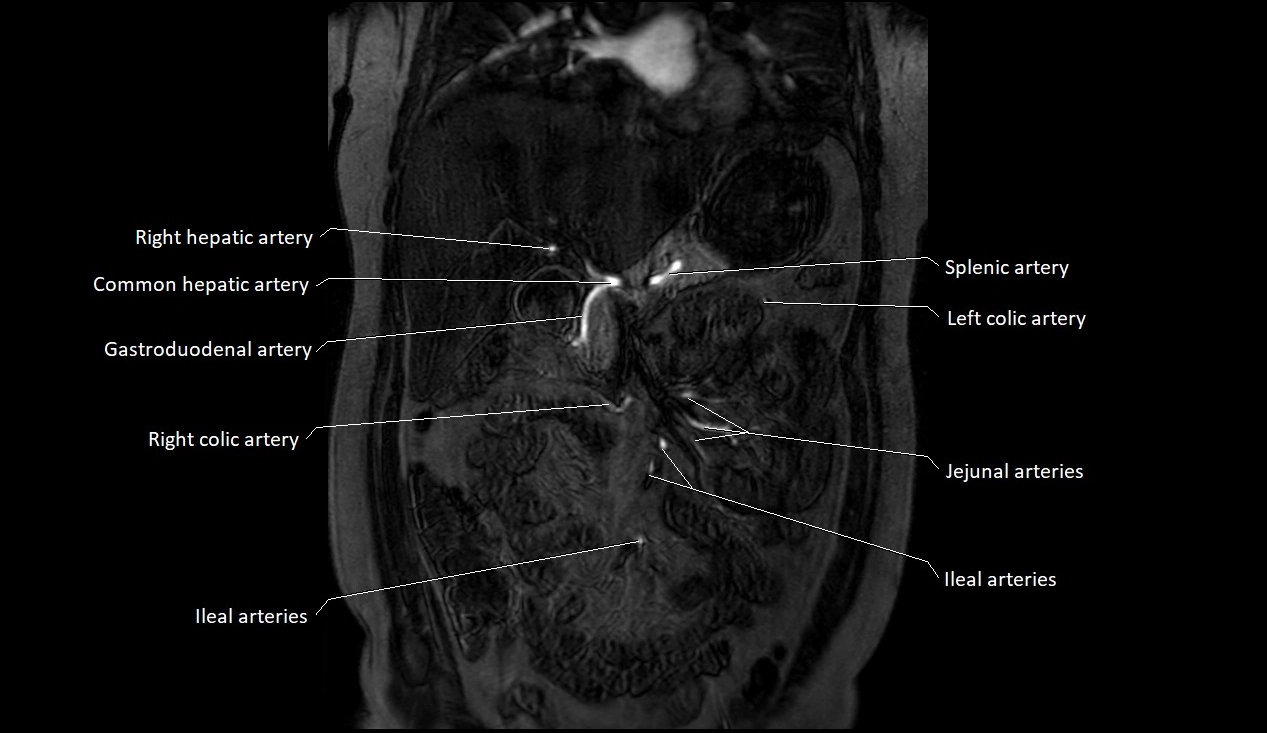

MRA (Magnetic Resonance Angiography):

• Contrast-enhanced MRA provides high-resolution imaging of the aorta and its branches

• Allows 3D reconstruction of visceral, parietal, and terminal branches

• Excellent for evaluating aneurysm size, dissection flap, stenosis, or preoperative planning

• Non-invasive alternative to conventional angiography

MRI images

image